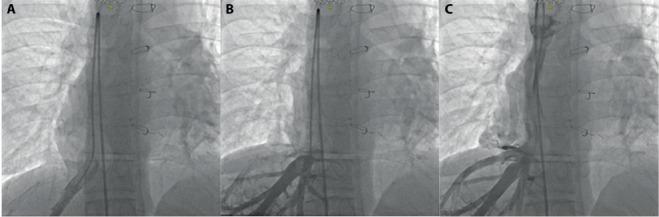

多模态影像学评估罕见且复杂的单心室生理学病例;心脏磁共振的重要作用。

Multi-modality Imaging Evaluation of a Rare and Complex Case of Single Ventricle Physiology; the important role of Cardiac MR.

Congenital heart diseases (CHD) represent a major clinical and diagnostic challenge for correct abnormality identification and subsequent successful therapy; even more challenging is following-up patient health after multiple post-interventional corrections often required in complex cardio-vascular abnormalities. We describe a multi-modality imaging evaluation of a complex congenital cardio-vascular diseases, underlining the relevance of cardiac magnetic resonance to non invasively solve some issues related to postsurgical changes.

先天性心脏病(CHD)是正确识别异常并随后成功治疗的主要临床和诊断挑战;更具挑战性的是在复杂心血管异常通常需要多次介入矫正后,对患者健康进行随访。我们描述了一种复杂先天性心血管疾病的多模态成像评估,强调心脏磁共振在无创解决与手术后变化相关的一些问题方面的相关性。